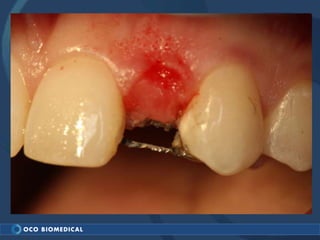

A 3.0mm dental implant was placed to replace congenitally missing maxillary lateral incisors. Dr. Tim Kosinski used a 1.8mm pilot bur and tissue punch to prepare the osteotomy site, then placed the implant by hand and seated it with a torque wrench. After ensuring the implant trajectory was within the restorative envelope, an acrylic coping was placed for temporary fabrication. At the 1 week post-op appointment, excellent soft tissue response and papilla formation were observed, and a final impression was taken to send to the lab for crown fabrication.